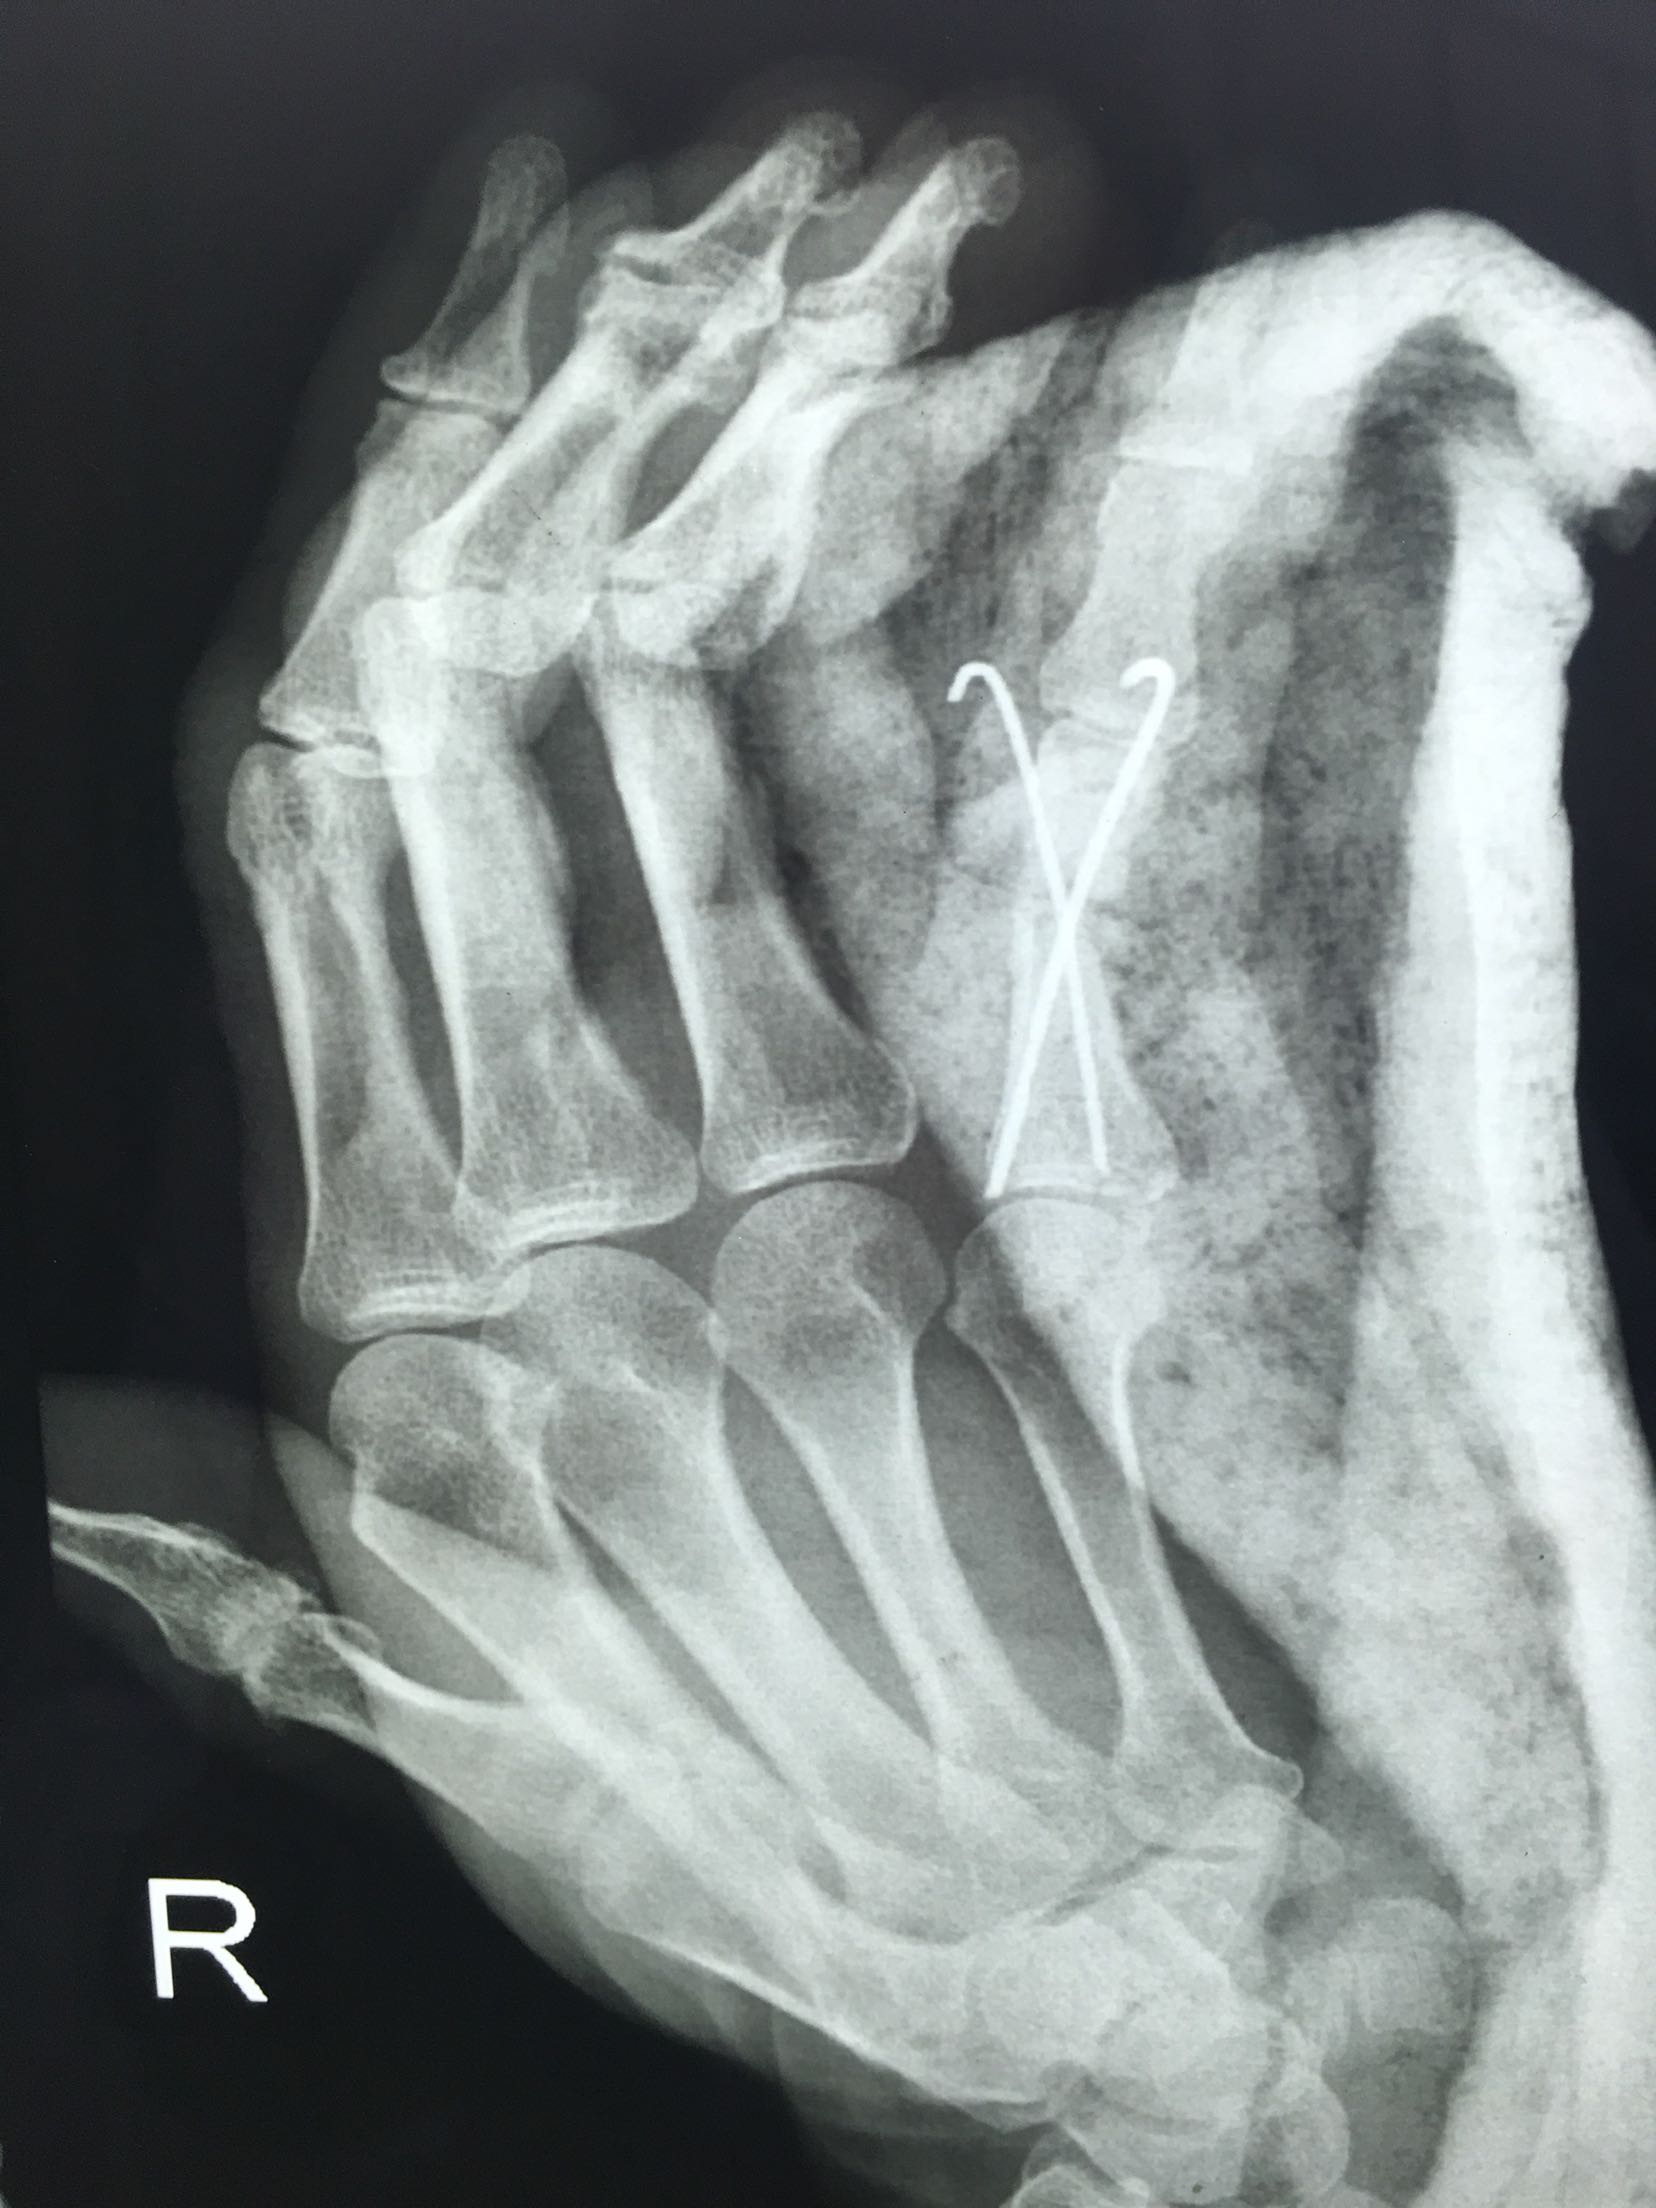

右小指开放性骨折

诊断 处理

急诊在臂丛麻醉下清创,探查吻合,骨折内固定术。术后石膏托固定3

一4周。